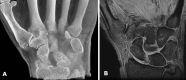

Methods: We addressed the morphology, load, and movement of the human thumb, emphasizing the CMC joint in normal and arthritic states. We present comparative anatomy, gross dissections, microscopic analysis, multimodal imaging, and live-subject kinematic studies to support or challenge the current understanding of the thumb CMC joint and its predisposition to disease.

Results: The current evidence suggests structural differences and loading characteristics predispose the thumb CMC to joint degeneration, especially related to volar or central wear. The patterns of degeneration, however, are not consistently identified, suggesting influences beyond inherent anatomy, repetitive load, and abnormal motion.